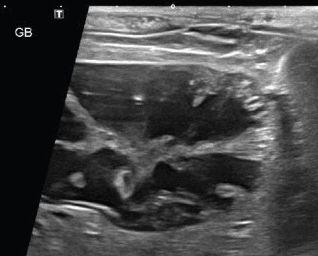

담석

담낭점액종

05선명한 초음파 영상 심장/응급초음파 포함, 장기 내부이상에 정확, 빠른 진단이 가능